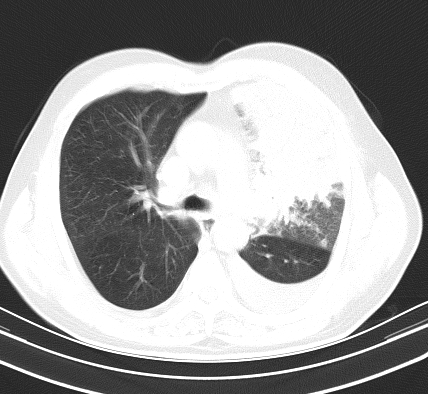

以下是引用老爱克斯新网客在2008-7-31 6:30:00的发言:[br]左肺上叶大片状病灶,左肺上叶支气管狭窄呈鼠尾状,左肺门增大,纵隔内见肿大淋巴结,左侧胸腔积液,余肺清晰。左肺中心型肺癌淋巴结转移,

以下是引用zjb在2008-7-31 6:32:00的发言:[br]左侧中心性肺癌 阻塞性肺炎 肺不张 胸腔积液 建议气管镜

以下是引用zjzjr在2008-7-31 8:45:00的发言:[br]考虑左侧中心性肺癌伴阻塞性肺炎,左肺上叶肺不张,纵隔淋巴结转移;左侧胸腔积液。建议行纤支镜检查。

以下是引用sdzyy在2008-7-31 8:47:00的发言:[br]病灶较治疗前有所进展,胸水增多, 左侧中心性肺癌 并 阻塞性肺炎 肺不张 胸腔积液 可能性大; 建议气管镜检查。 [br] [br]